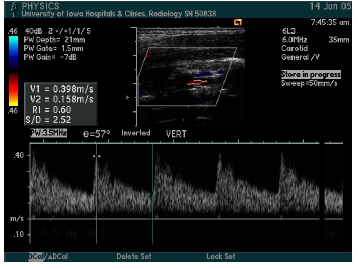

what vessel is this waveform likely from?

CCA (below is distal CCA)

ICA (proximal), below is distal